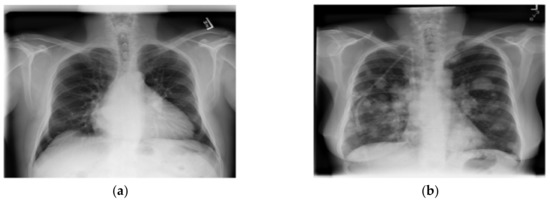

2.2. Dataset